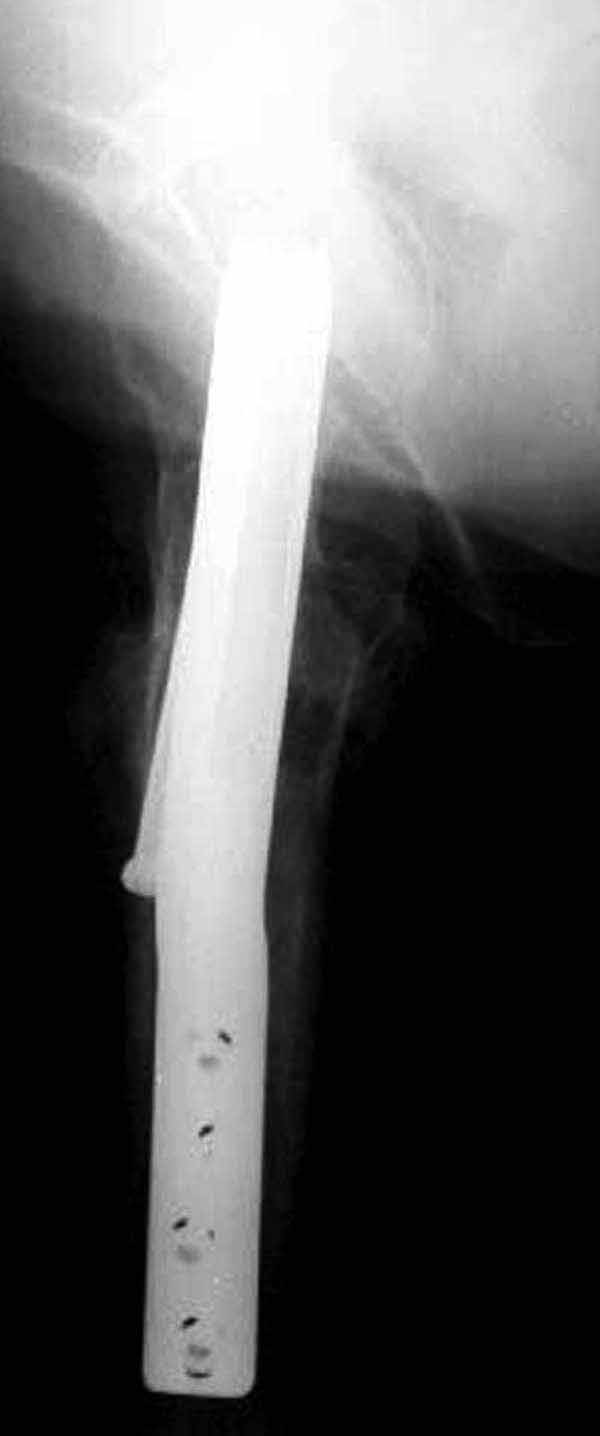

Здесь подобный случай, где стрессовый перелом обнаружен через 2 недели после фиксации. Применен Blade Plate с дополнительными шурупами.

У больных с ожирением и соматическими заболеваниями нежелательно открывать место перелома. Гвозди от DePuy с двумя шурупами рассчитаны для переломов бедра, и приходилось их применить для фиксации подвертельных переломов, но более адекватную фиксацию создает Gamma 3.

Согласен с Николаем, винты распоожены так, чтобы эту "мину" заложить. И два внизу, и не должны, даже если один он там, они входить ниже уровня малого вертела, это резко повышает риск подвертельного перелома. Что до остеосинтеза - учитывая 76 лет, более подходящей представляется большего диаметра винт в шейке, то есть гамма.

3. Чем фиксировать: я бы выбрал второй вариант